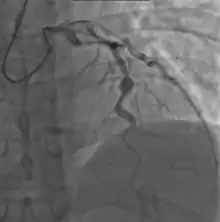

- Angiography was historically used to detect coronary artery aneurysms, and remains the gold standard for their detection, but is rarely used today unless coronary artery aneurysms have already been detected by echocardiography.

Heart complications are the most important aspect of Kawasaki disease, which is the leading cause of heart disease acquired in childhood in the United States and Japan.[31] In developed nations, it appears to have replaced acute rheumatic fever as the most common cause of acquired heart disease in children.[15] Coronary artery aneurysms occur as a sequela of the vasculitis in 20–25% of untreated children.[52] It is first detected at a mean of 10 days of illness and the peak frequency of coronary artery dilation or aneurysms occurs within four weeks of onset.[48] Aneurysms are classified into small (internal diameter of vessel wall <5 mm), medium (diameter ranging from 5–8 mm), and giant (diameter > 8 mm).[31] Saccular and fusiform aneurysms usually develop between 18 and 25 days after the onset of illness.[15]

Many risk factors predicting coronary artery aneurysms have been identified,[21] including persistent fever after IVIG therapy,[56][57] low hemoglobin concentrations, low albumin concentrations, high white-blood-cell count, high band count, high CRP concentrations, male sex, and age less than one year.[58] Coronary artery lesions resulting from Kawasaki disease change dynamically with time.[3] Resolution one to two years after the onset of the disease has been observed in half of vessels with coronary aneurysms.[59][60] Narrowing of the coronary artery, which occurs as a result of the healing process of the vessel wall, often leads to significant obstruction of the blood vessel and the heart not receiving enough blood and oxygen.[59] This can eventually lead to heart muscle tissue death, i.e., myocardial infarction (MI).[59]

Laboratory evidence of increased inflammation combined with demographic features (male sex, age less than six months or greater than eight years) and incomplete response to IVIG therapy create a profile of a high-risk patient with Kawasaki disease.[58][149] The likelihood that an aneurysm will resolve appears to be determined in large measure by its initial size, in which the smaller aneurysms have a greater likelihood of regression.[150][151] Other factors are positively associated with the regression of aneurysms, including being younger than a year old at the onset of Kawasaki disease, fusiform rather than saccular aneurysm morphology, and an aneurysm location in a distal coronary segment.[60] The highest rate of progression to stenosis occurs among those who develop large aneurysms.[3] The worst prognosis occurs in children with giant aneurysms.[152] This severe outcome may require further treatment such as percutaneous transluminal angioplasty,[153] coronary artery stenting,[154] bypass grafting,[155] and even cardiac transplantation.[156]